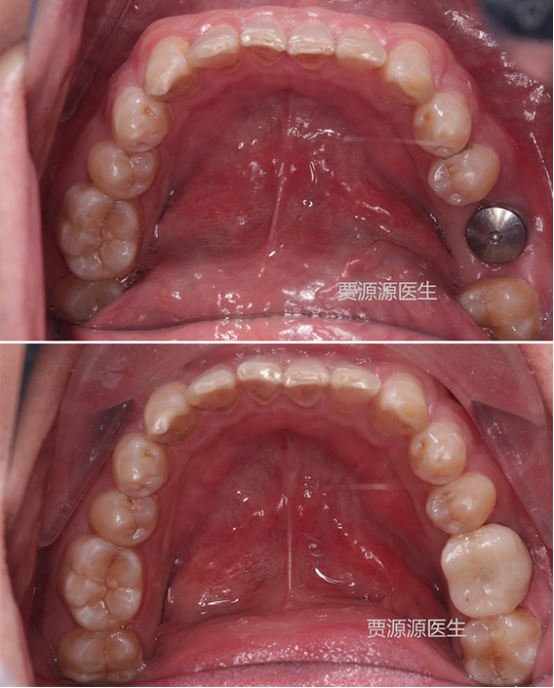

(种植修复)